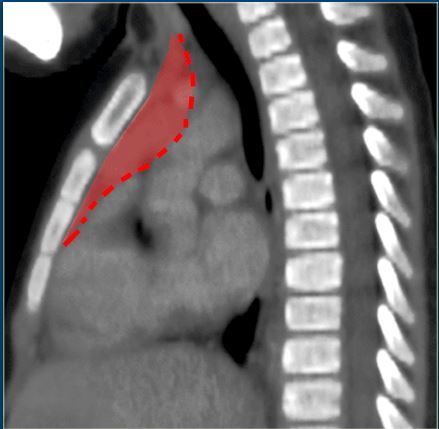

3. 谢大夫,这个前纵隔占位,是胸腺瘤吗?

回答:这是一个胸骨后甲状腺,不是胸腺瘤,它从颈部一直下降坠落到胸腔里。